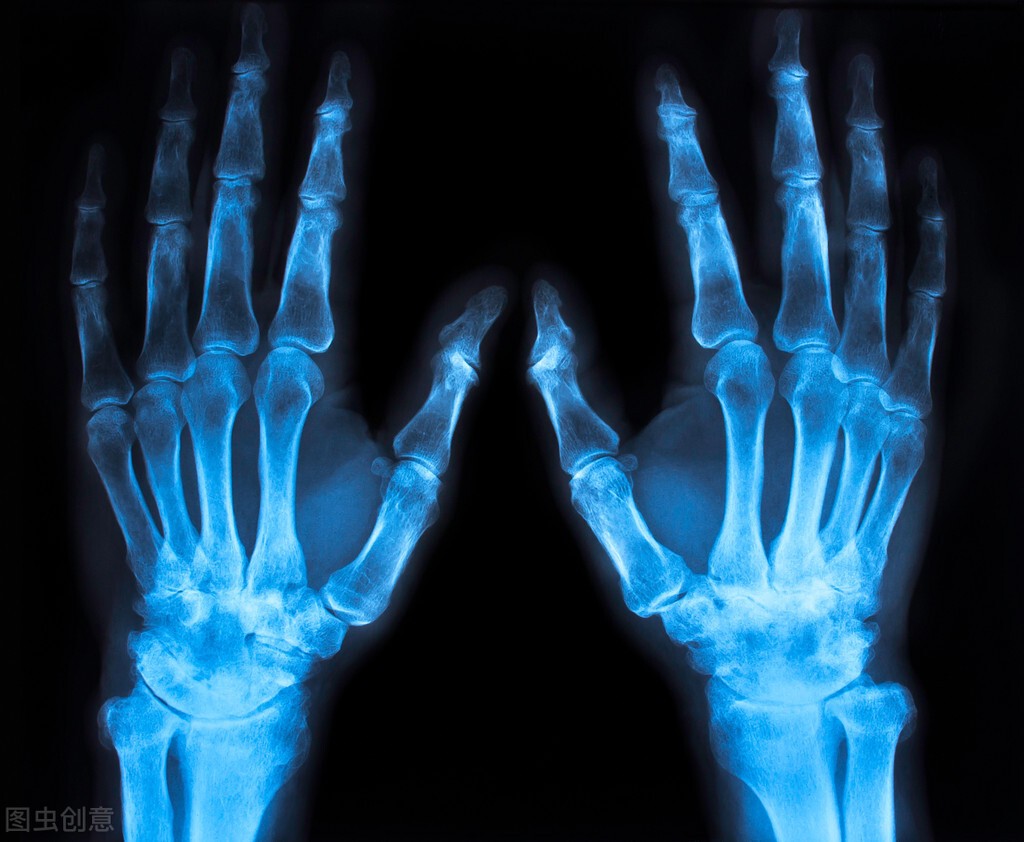

类风湿性关节炎是一种非常常见的、全身的、慢性的自身免疫性疾病,40岁以后高发,是致残率非常高的一种关节炎,常累及身上的一些小关节,尤其是掌指关节、近端指间关节、腕关节。

患上类风湿性关节炎后,早期,患者多表现为关节游走性疼痛、肿胀和功能障碍,等到了晚期,患者会出现明显的关节僵硬、畸形、骨骼肌萎缩,甚至还可能出现心、肺、肾、周围神经及眼的内脏病变。

(2)持续4~ 6周以上的对称性关节肿大,且多集中在腕、掌指关节或近端指关节上。

(5)手部X光片有典型的囊性骨侵蚀,关节面模糊,关节间隙狭窄。